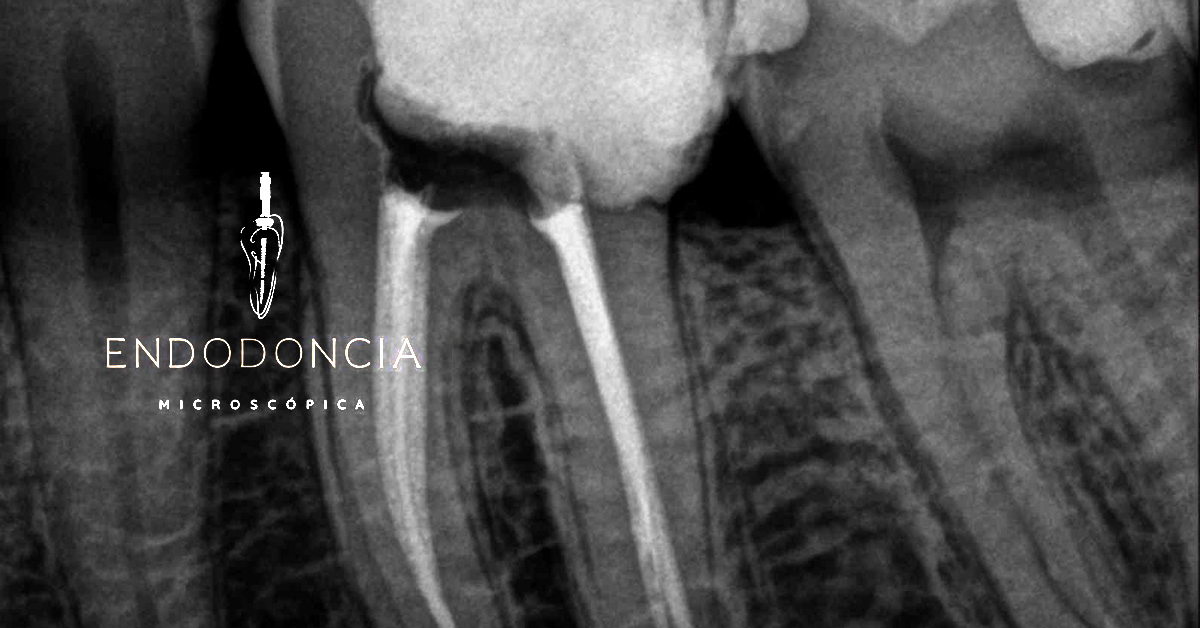

Diagnóstico avanzado

Radiografías digitales intraorales y tomografía de haz cónico para valorar la anatomía dental en 3D. Imágenes de alta resolución nos permiten detectar fracturas, reabsorciones o conductos calcificados antes del tratamiento.

Tratamiento de conducto complejo

Los molares suelen tener múltiples canales o anatomía complicada. En estos casos usamos microscopio quirúrgico o lupas potentes para localizar todos los conductos y atenderlos con precisión. Usamos instrumentos avanzados, lo que reduce el riesgo de fractura de instrumentos y acorta el tiempo de tratamiento.